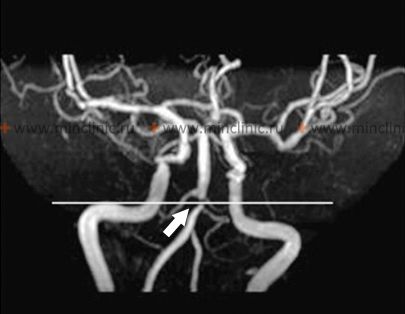

სისხლძარღვოვანი ვიზუალიზაცია: აუცილებელია სისხლძარღვოვანი დაზიანების ლოკაციის და ბუნების (სტენოზი, ოკლუზია, დისექცია, ანევრიზმა) იდენტიფიცირებისთვის [5].

- კტ ანგიოგრაფია (CTA): ფართოდ ხელმისაწვდომი და სწრაფად შესრულებადია, ხშირად არაკონტრასტული კტ-ის შემდეგ დაუყოვნებლივ[5]. მოიცავს ინტრავენური კონტრასტის შეყვანას არტერიების ვიზუალიზაციისთვის. CTA უზრუნველყოფს დიდი სისხლძარღვების კარგ დეტალებს, მათ შორის ხერხემლისა და ძირითადი არტერიების, და შეუძლია აღმოაჩინოს მნიშვნელოვანი სტენოზი ან ოკლუზია [5]. შედარებითი უკუჩვენებები მოიცავს მძიმე ალერგიას კონტრასტზე და თირკმლის მნიშვნელოვან უკმარისობას.

- მრ ანგიოგრაფია (MRA): შეიძლება შესრულდეს მაიონიზებელი გამოსხივების ან იოდირებული კონტრასტის გარეშე (თუმცა გადოლინიუმის კონტრასტი ხშირად გამოიყენება უკეთესი დეტალებისთვის, თავისი საკუთარი უკუჩვენებებით, როგორიცაა თირკმლის მძიმე უკმარისობა) [5, 7]. უზრუნველყოფს ვერტებრობაზილარული სისტემის კარგ ვიზუალიზაციას, მაგრამ შეიძლება იყოს ნაკლებად ზუსტი, ვიდრე CTA ან DSA სტენოზის სიმძიმის რაოდენობრივად შესაფასებლად [7].